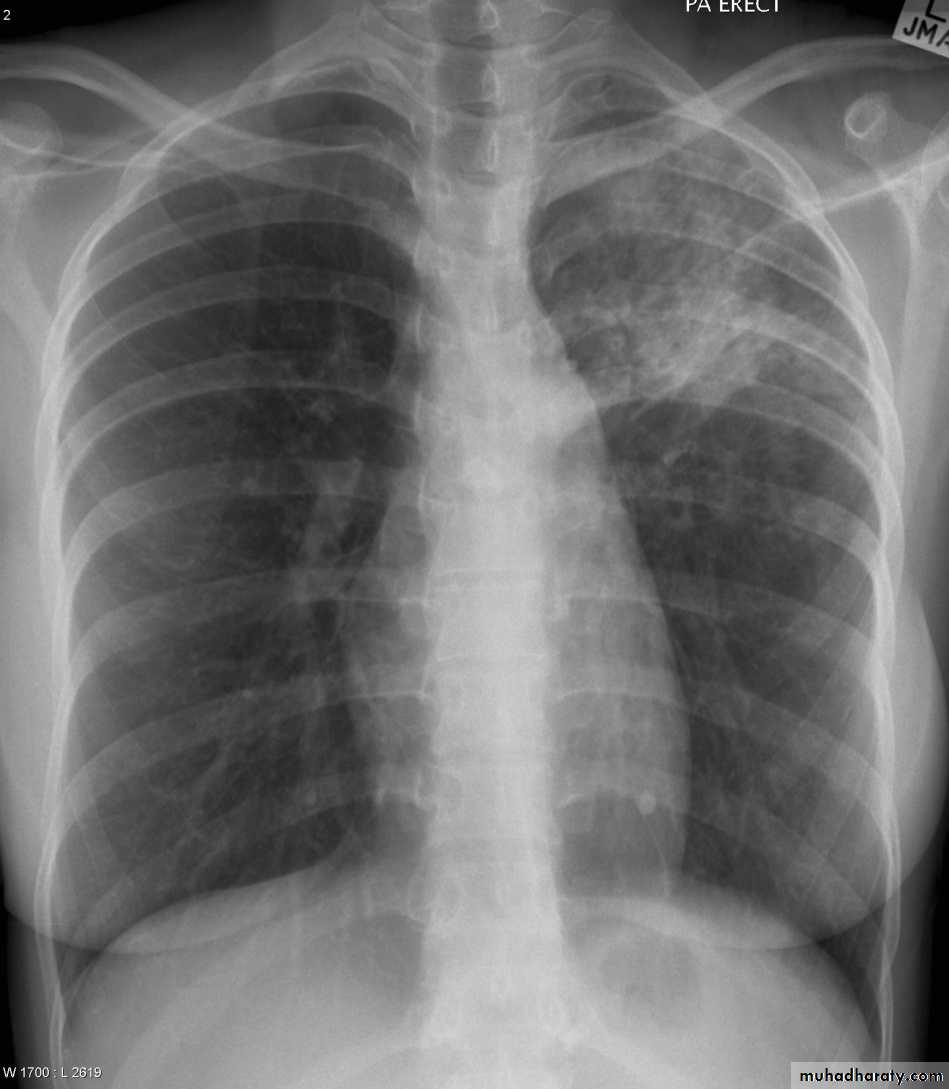

The pleura :

• Pleural effusion : collection of fluid within the pleural space. This can be further divided into Transudate , exudate, according to protein content .Other type of fluid collection within pleural space are

• Chest x-rays are the most commonly used examination to assess for presence of a pleural effusion, however it should be noted that on a routine erect frontal chest x-ray as much as 200-500 ml of fluid is

• required before it becomes evident .

blunting of the costophrenic angle

blunting of the cardiophrenic angle

fluid within the horizontal or oblique fissures

eventually a meniscus will be seen, on frontal films seen laterally and gently sloping medially

with large volume effusions, mediastinal shift occurs away from the effusion

• Lateral films are able to identify a smaller amount of fluid ( about75%)as the costophrenic angles are deepest posteriorly posteriorly